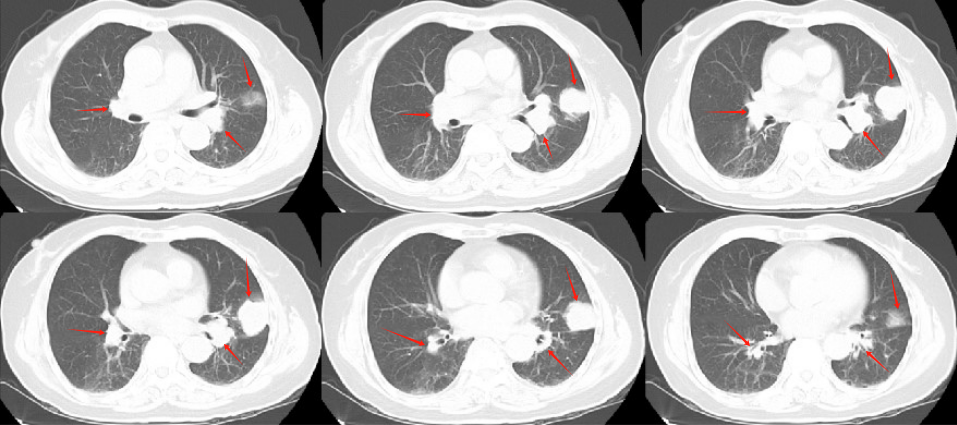

張老太,70歲, 2024年8月因頭暈頭痛,頻繁嘔吐等癥狀入院。頭部磁共振檢查顯示,顱內(nèi)多發(fā)腦轉(zhuǎn)移瘤病灶(見圖)。同時(shí),患者胸部CT檢查可見肺內(nèi)多發(fā)較大腫瘤病灶(見圖)?;颊哂?024年8月20日行CT引導(dǎo)肺腫物穿刺活檢。病理診斷為肺腺癌。綜合診斷為肺腺癌IVB期,腦、肺內(nèi)、右腎上腺多發(fā)轉(zhuǎn)移?;颊哌M(jìn)一步行腫瘤組織基因檢測(cè)和免疫檢查點(diǎn)分子——細(xì)胞程序性死亡配體1(PDL1)檢測(cè)。

圖注:胸部CT檢查,肺內(nèi)多發(fā)較大腫瘤病灶。

患者于2024年08月20開始接受頭部放療。采用最新一代智慧化精準(zhǔn)放療系統(tǒng)——Halcyon“速銳刀”,成功控制患者全部顱內(nèi)病灶,過程順利,沒有明顯副反應(yīng)發(fā)生。患者基因檢測(cè)結(jié)果為陰性,沒有找到具有靶向治療藥物的突變基因。此外,患者年齡較大,體質(zhì)較弱,全身多發(fā)轉(zhuǎn)移病灶,為治療帶來了巨大的挑戰(zhàn)。然而,患者PDL1檢測(cè)顯示,PDL1高表達(dá)(PD-L1 TPS=98%),提示免疫治療有效率較高。潘振宇教授團(tuán)隊(duì)為患者制定了個(gè)體化精準(zhǔn)腫瘤治療方案,僅僅每3周應(yīng)用1次免疫治療藥物。經(jīng)過3次治療后復(fù)查,患者肺內(nèi)病灶顯著縮退,顱內(nèi)病灶縮退。治療過程中,僅出現(xiàn)一過性皮疹。目前患者恢復(fù)良好,生活完全自理。

圖注:治療后復(fù)查胸部CT顯示,肺內(nèi)病灶明顯縮小。